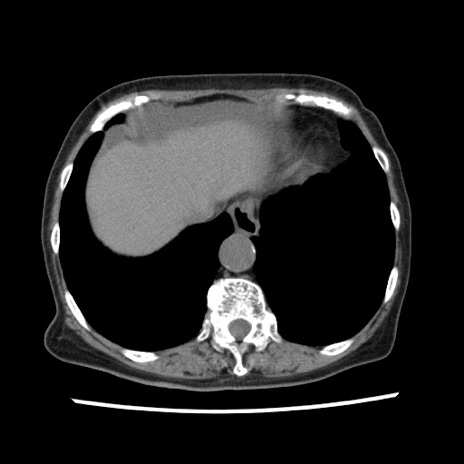

冠状断像